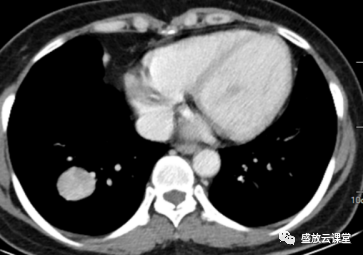

增强CT影像表现

右肺下叶基底段类圆形高密度影,大小约3.0cm×2.9cm

边缘规整,其内见点状钙化,增强扫描明显均匀强化

密度:密度较均匀,其内见点状钙化

强化方式:均匀强化

影像学特点(CT):右肺下叶基底段类圆形高密度影,边缘规整,密度较均匀,其内见点状钙化,增强扫描明显均匀强化